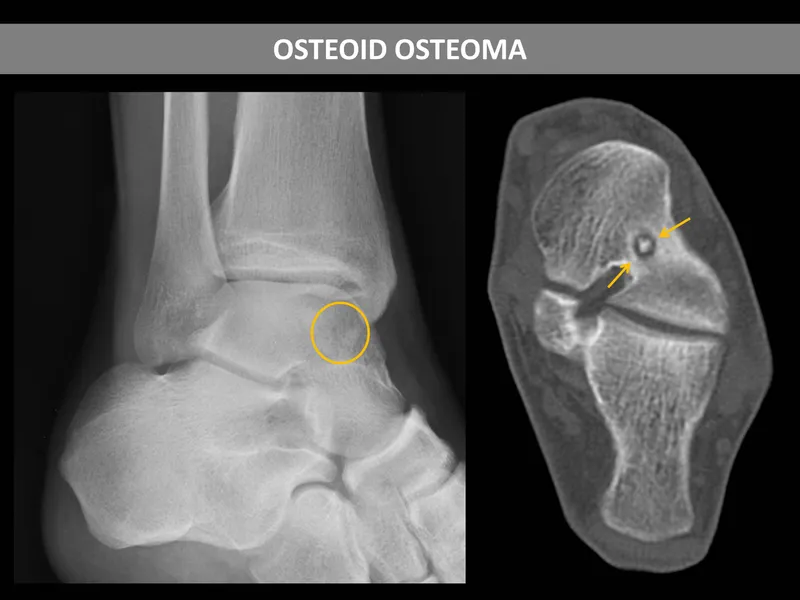

- Osteoid Osteoma:

- Age: < 30 yrs. Long bones (femur, tibia), spine.

- Pain: Nocturnal, severe, localized.

⭐ Osteoid osteoma pain is classically relieved by NSAIDs due to prostaglandin E2 production by the nidus.

- X-ray: Radiolucent nidus (< 1.5-2 cm) with surrounding reactive sclerosis.

- Tx: Radiofrequency Ablation (RFA), surgical excision.